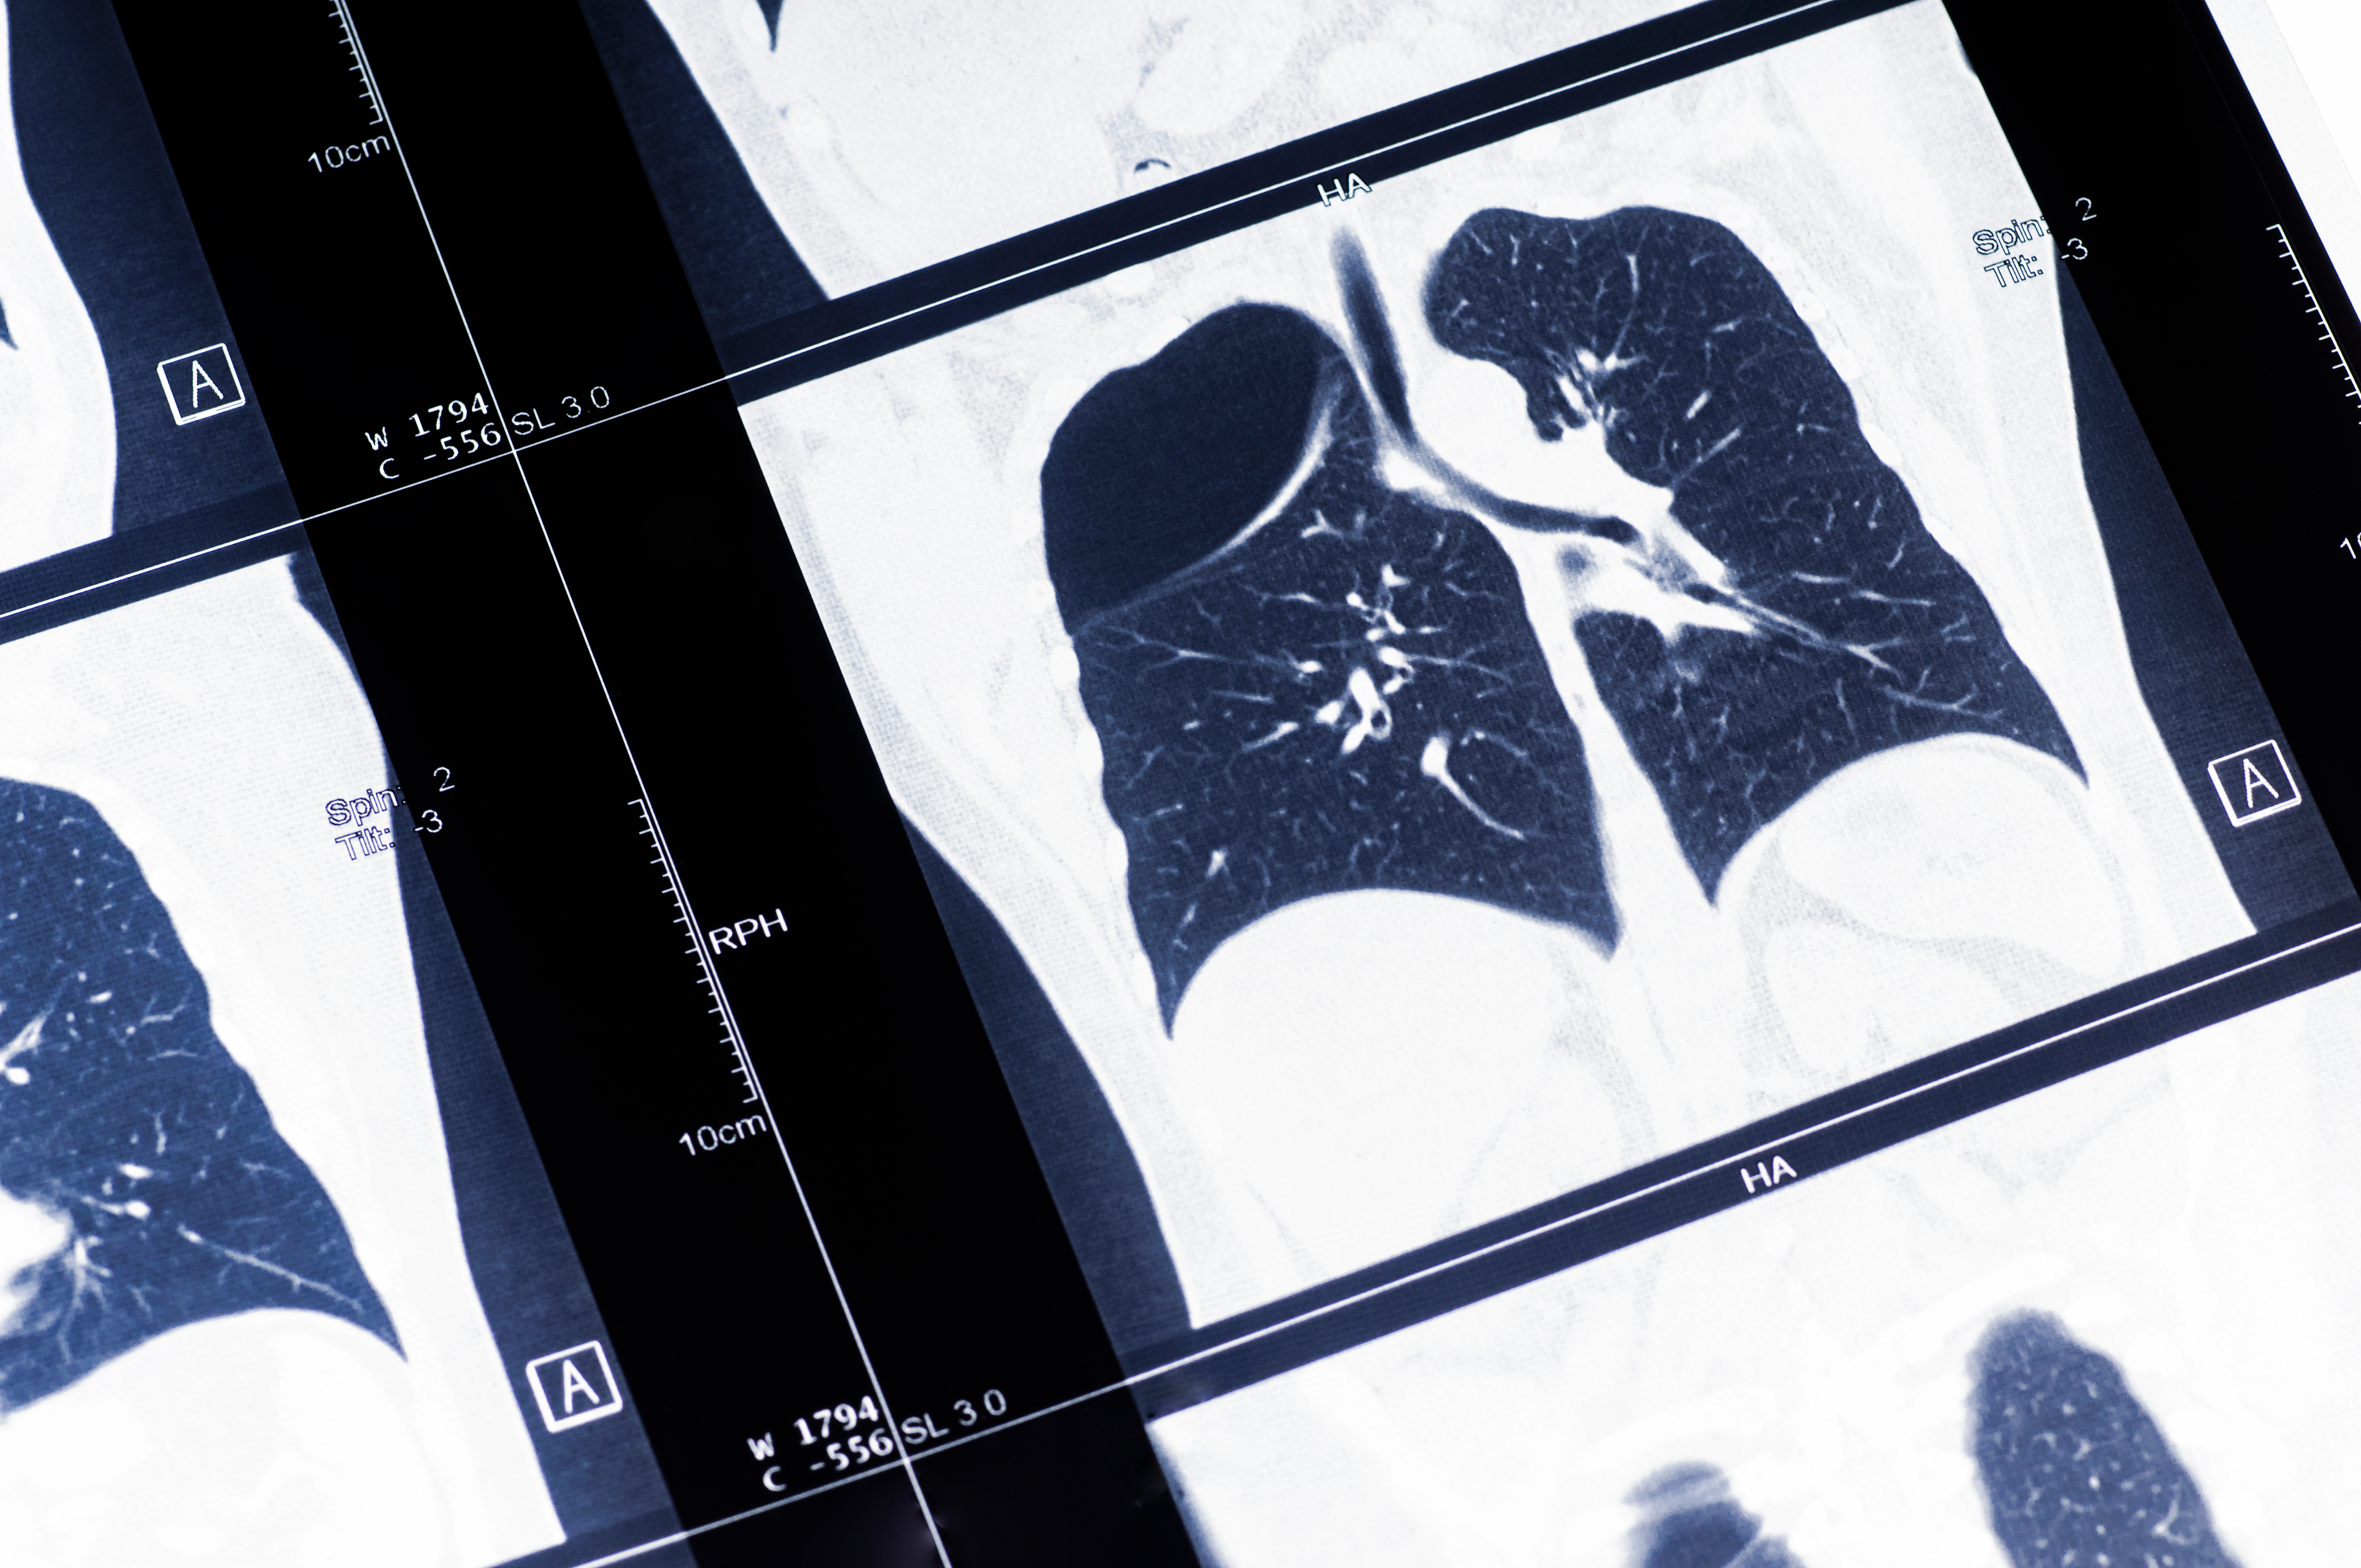

It is estimated that 550 million people worldwide live with chronic lung disease, demonstrating the significant demand for medical imaging to aid in early diagnosis. Providing an enhanced image of the lungs may help a variety of patients suffering from lung diseases, including idiopathic pulmonary fibrosis, COPD, pulmonary hypertension, radiation therapy, cystic fibrosis and asthma.